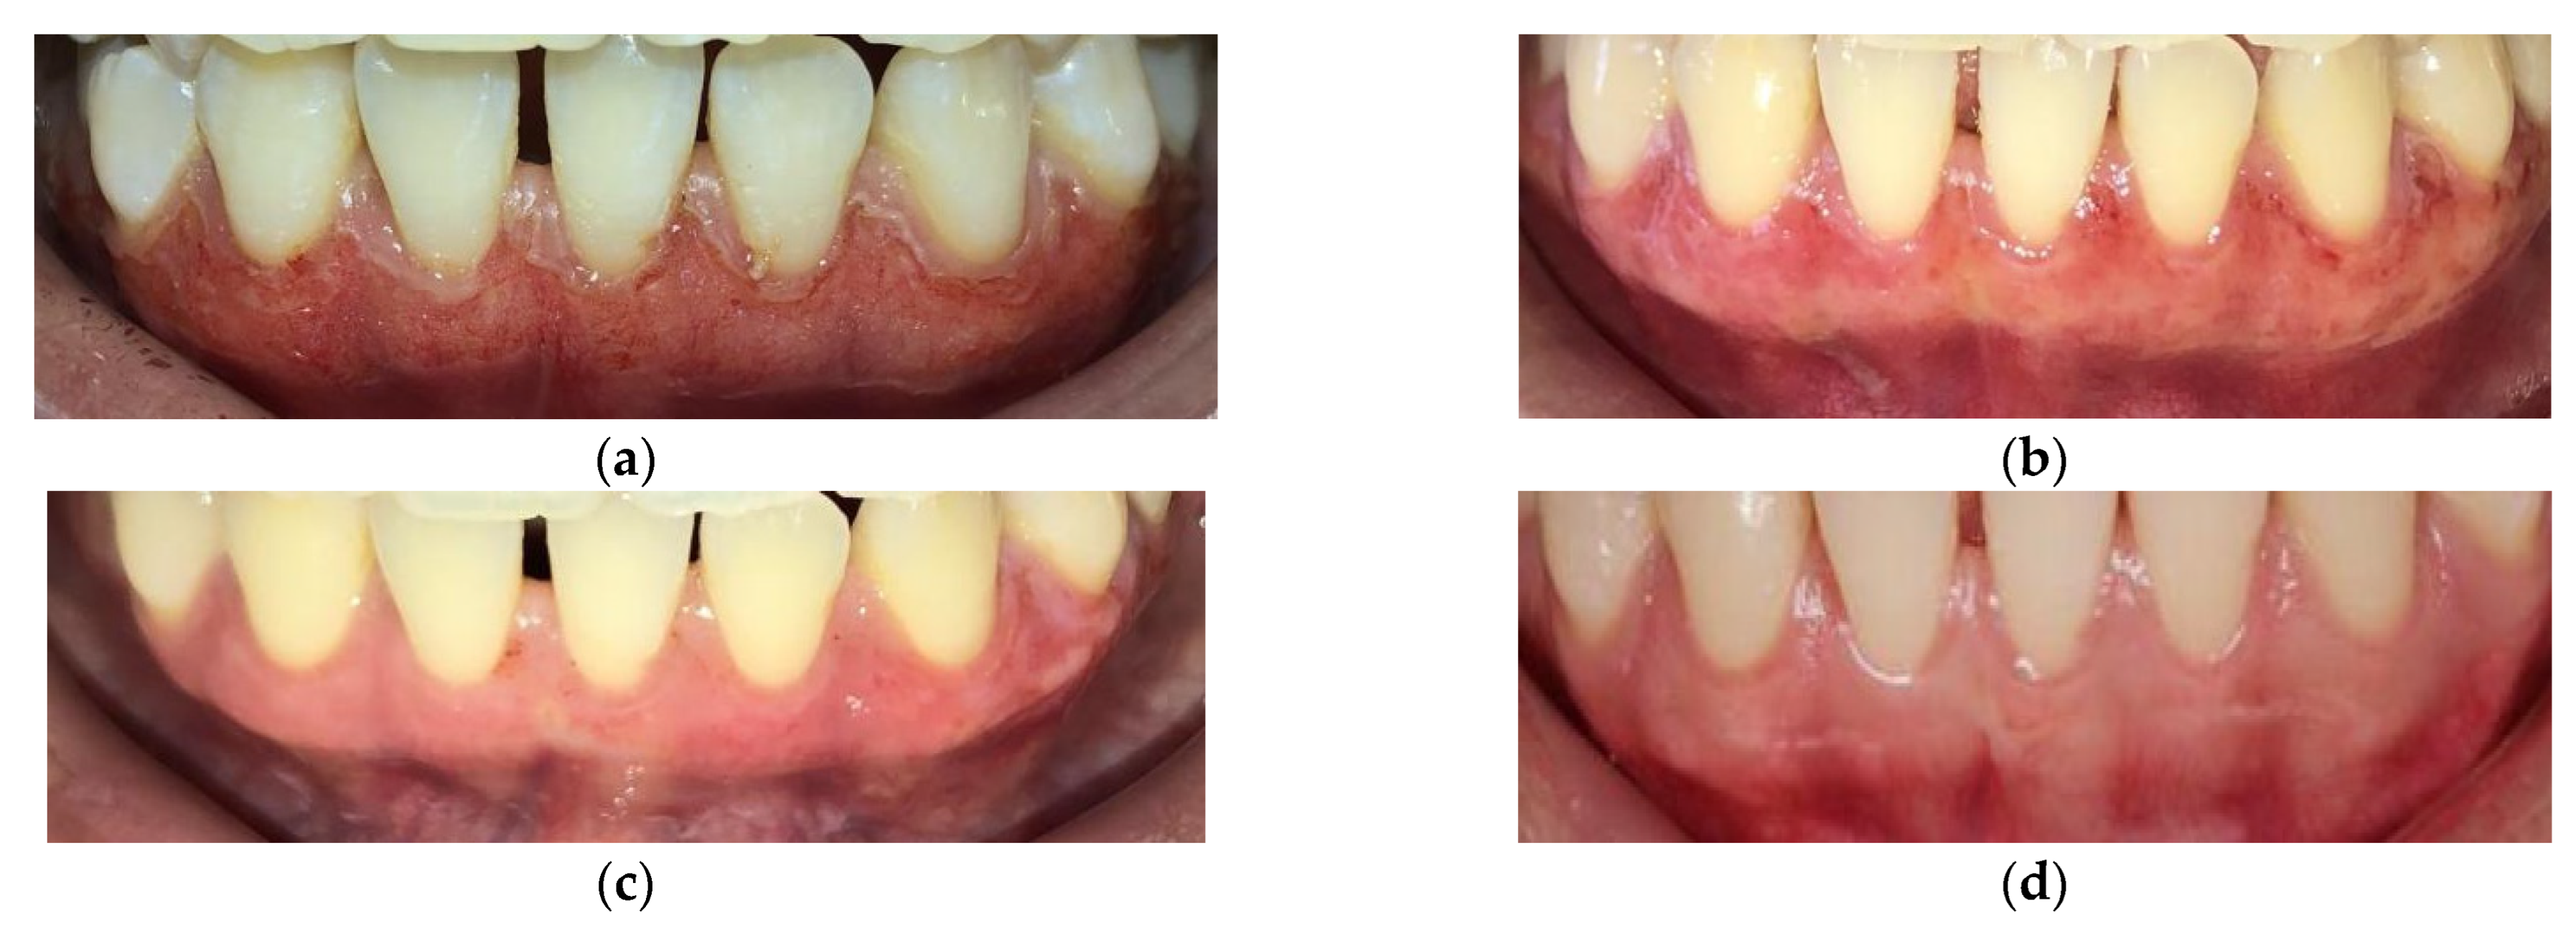

3.4. Gingival Pigmentation According to DOPI after Treatment

| Variable | Baseline | 4 Weeks |

| Mean ± SD | 2.24 ± 0.79 | 0.97 ± 0.16 |

| p * | <0.001 | |